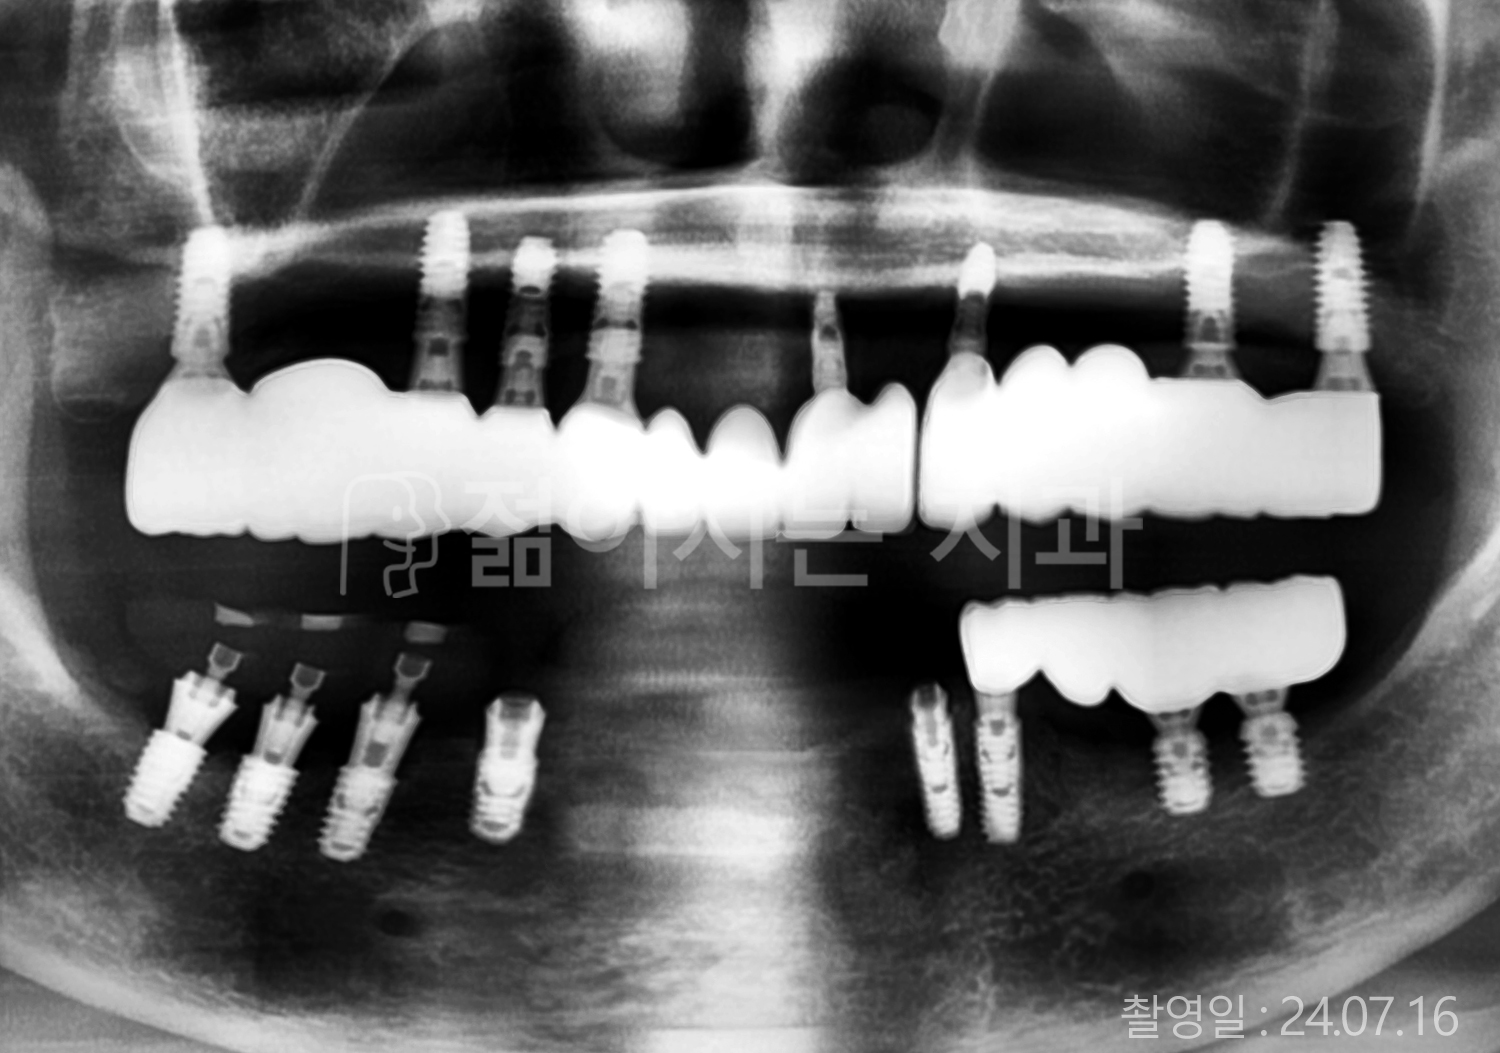

• 80대 전체치아 10개 이상 임플란트

• 60대 고혈압, 당뇨, 고지혈증 전체치아 10개 이상 임플란트

• 60대 전체치아 10개 이상 임플란트

• 60대 고혈압, 고지혈증 전체치아 10개 이상 임플란트

• 50대 고혈압, 당뇨, 고지혈증 전체치아 10개 이상 임플란트

• 70대 골다골증, 파킨스병 전체치아 10개 이상 임플란트

• 40대 전체치아 10개 이상 임플란트

• 60대 골다골증 전체치아 10개 이상 임플란트

• 40대 고혈압 전체치아 10개 이상 임플란트

• 50대 전체치아 10개 이상 임플란트

• 70대 전체치아 10개 이상 임플란트